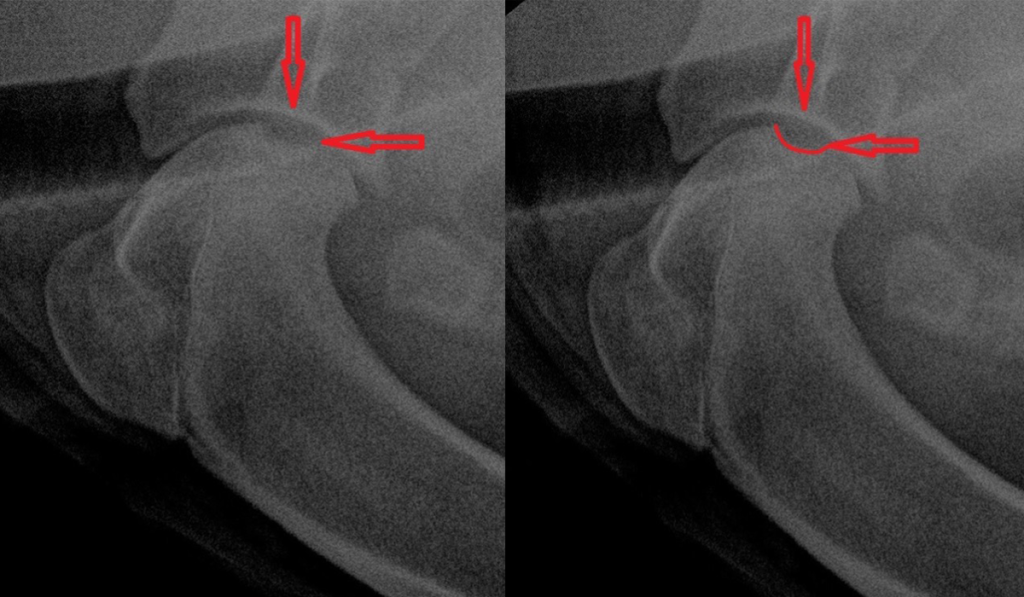

При проявлении РОХ отмечается прободение (ямка) по месту отслоения хряща, что приводит к снижению его плотности на фоне нарушения сосудистого питания и визуализируется на рентген снимке как ямка – отмечено красной линией.